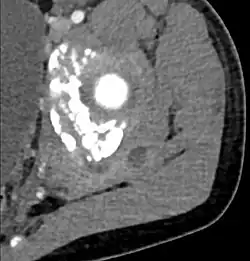

Additional images

CT exam showing a multiloculated fluid collection in the left gluteus minimus muscle found to be a staph aureus pyomyositis in a 12-year-old healthy boy.